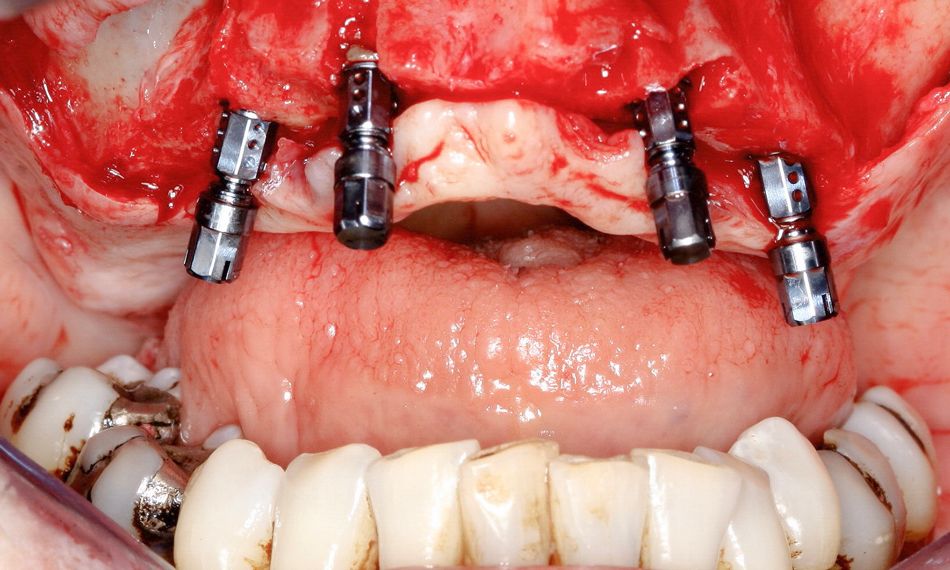

Local anesthesia with lidocaine 2% with epinephrine 1:100,000 was administered. A mucoperiosteal flap with a crestal incision was raised. The surgical stent was checked and positioned for implant placement, ensuring the proper positioning and angulation of the implants within the bone (Fig. 5). The alveolar bone was slightly reduced and flattened. The Straumann® Surgical Cassette was utilized to prepare the implant bed, following the pilot drilling protocol. Four Straumann® BL SLActive® implants were inserted, with straight implants positioned in the front and tilted implants at the back. Utilizing the handpiece at a maximum speed of 15 rpm, the implants were placed in a clockwise direction and torqued to 35 Ncm (Fig. 6).

Following implant placement, screw-retained 0°-straight and 30°-angulated abutments, and temporary abutments were placed to correct occlusal orientation (Fig. 7). Subsequently, the mucoperiosteal flap was meticulously adapted, wound closure was performed, and the impression could then be taken (Fig. 8).